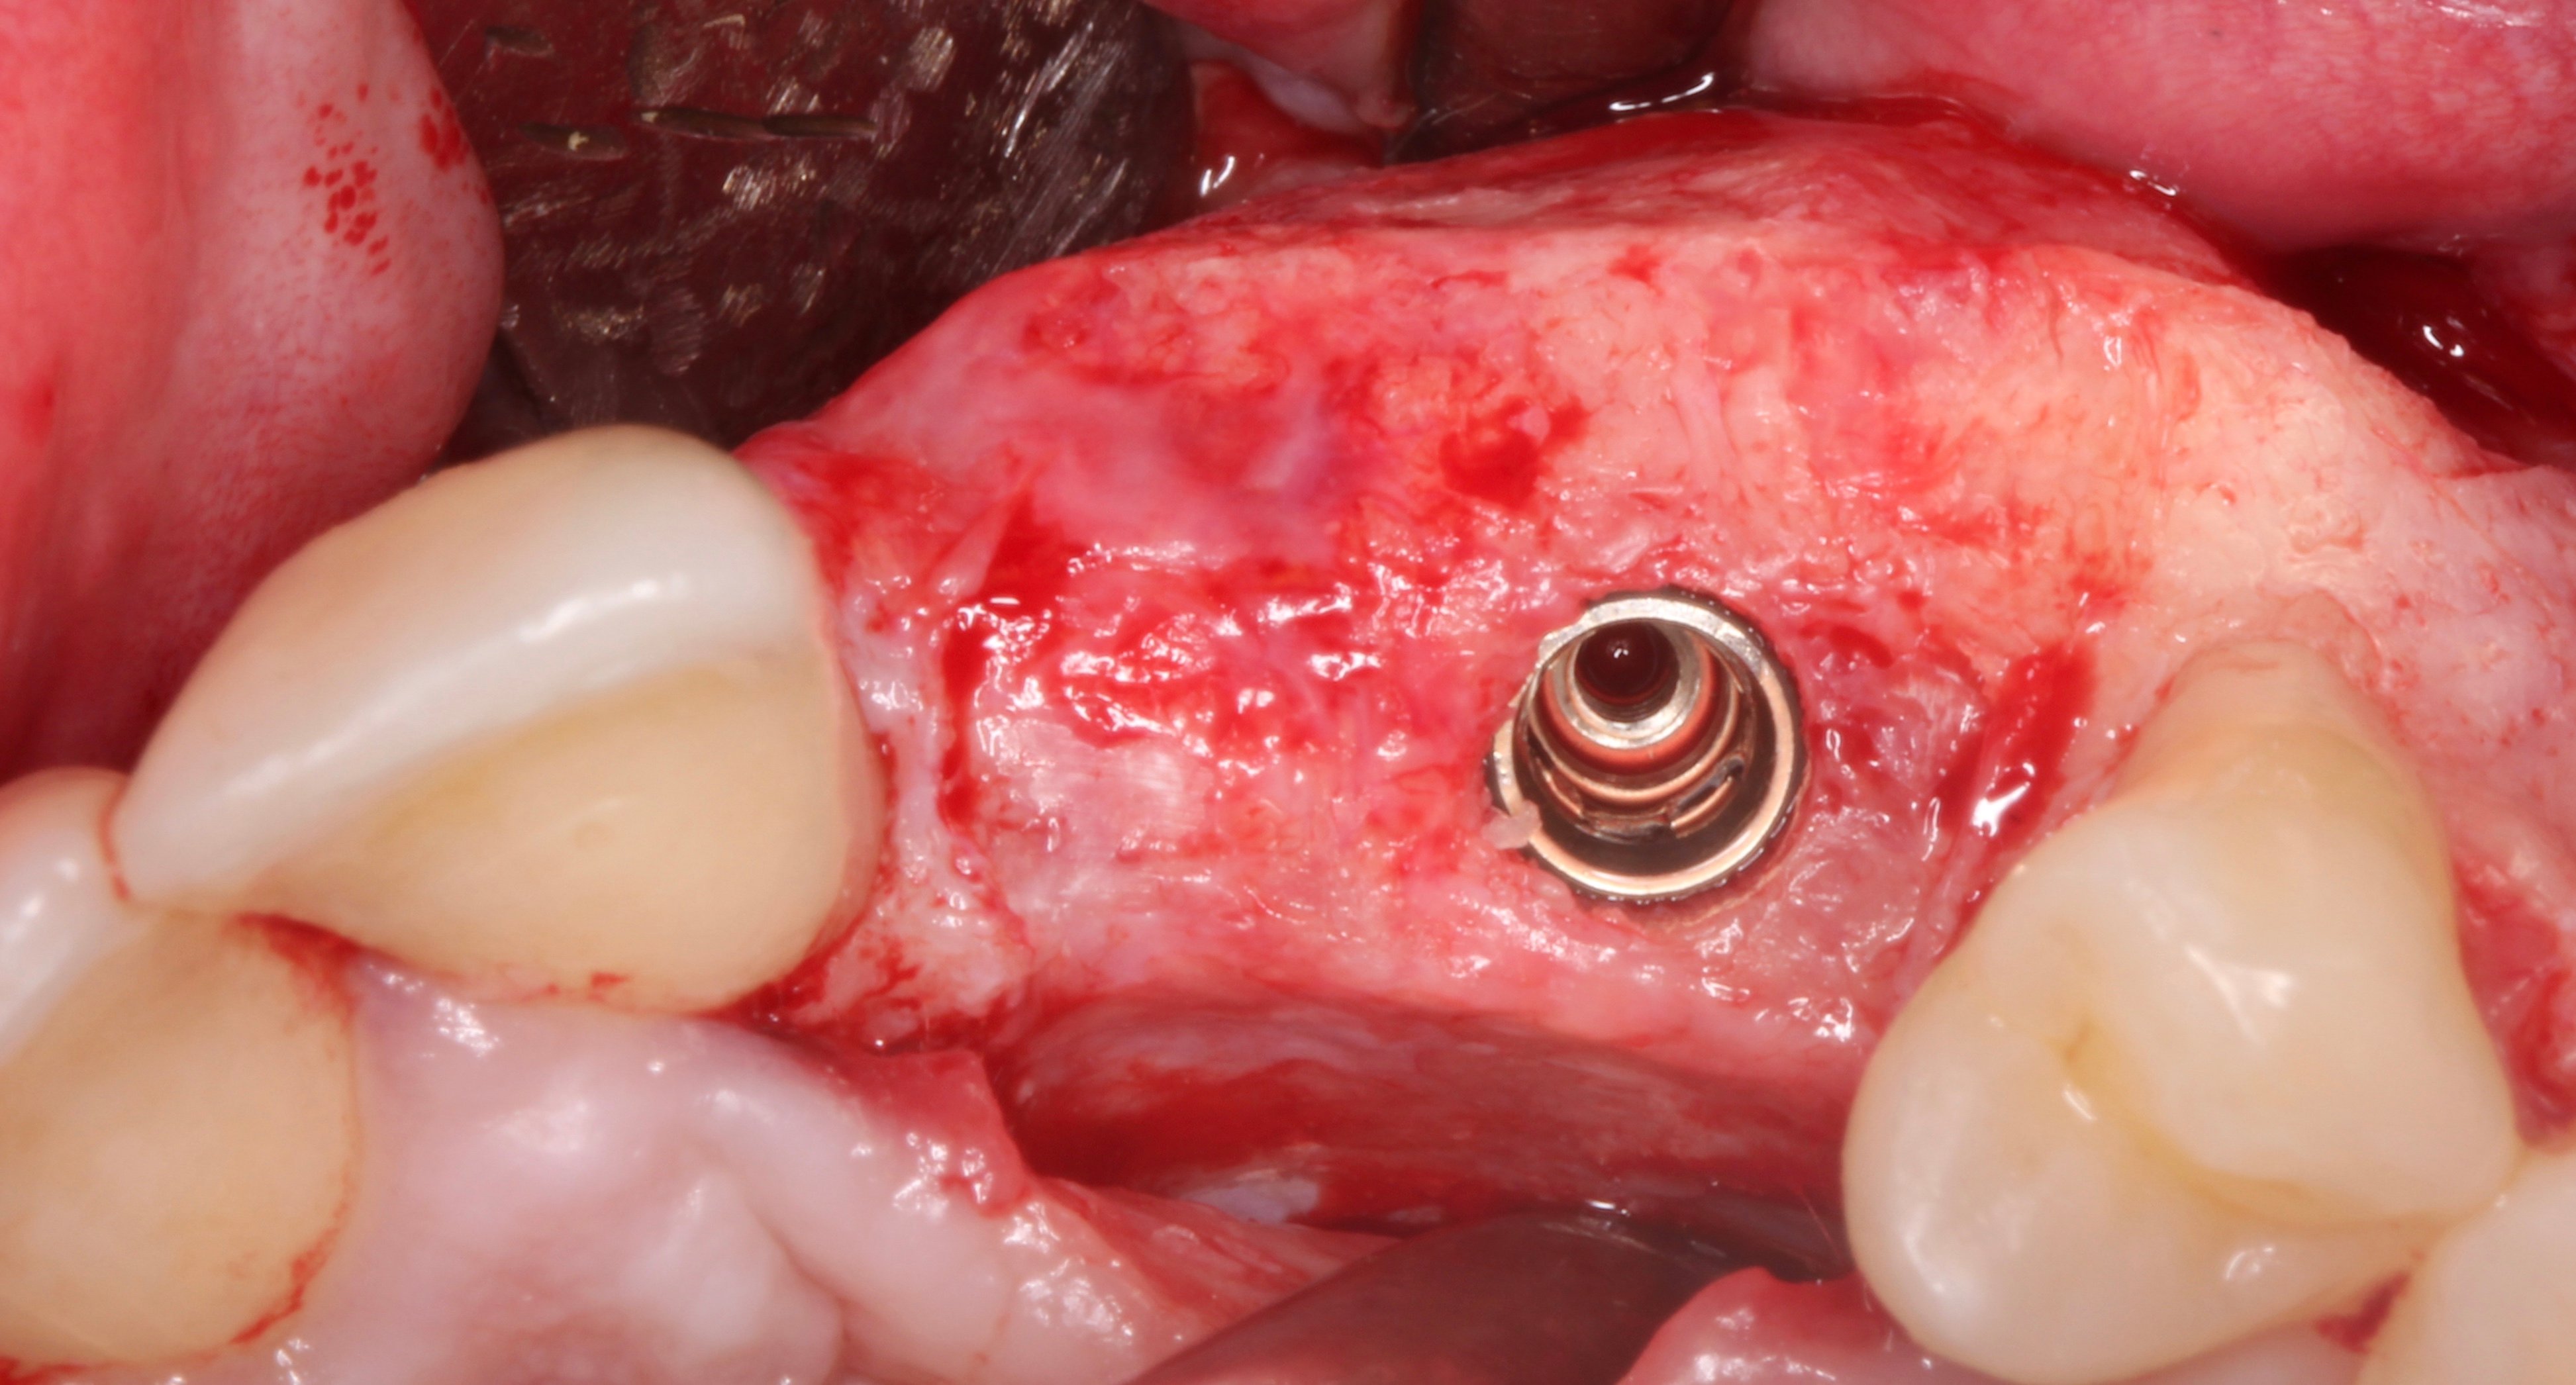

- 1 year later: Reentry and implant placement at 23 + connective tissue graft to solve the papilla loss at distal aspect of tooth 21.

- 2 months later: 2nd surgical phase and temporary restoration.

Step by step